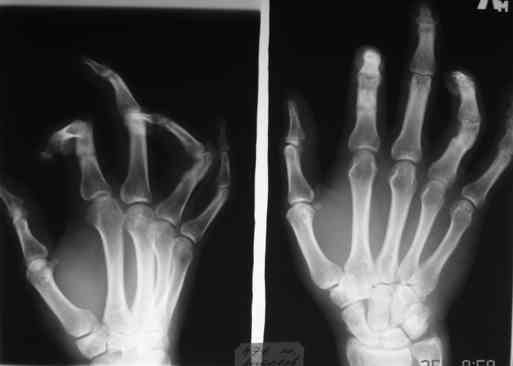

При размещении с рисунков "исчезли" подписи, поэтому дополнительно указываю, что первая рентгенограмма - снимок после травмы, вторая - состояие на сегодня. На мой взгляд контрактура прежде всего артрогенная, т.к. ПМФС 2-го и 4-го пальцев находятся в подвывихе. Движения, в существующем на сегодня объеме, свободные - даст-ли тендолиз ожидаемый эффект? Стоит-ли начать с аппарата внешней фиксации? Не приведет-ли одномоментный артролиз и последующая попытка вправления при длительно существовавшем подвывихе к раздавливанию суставными поверхностямя друг друга?

Для того, чтобы понять, действительно ли ПМФС находятся в подвывихе, надо сначала сделать четкую боковую рентгенографю сустава. Особенно это касается второго пальца. Да и на мониторе очень плохо видно состояние головки проксимальной фаланги 4 пальца. И что означает такой интересный объем движений в суставах? Объясните - существует ограничение только активных движений ( и каких?) или еще и пассивных?

Ограничение движений одинаковое и активных и пассивных. Движения в указанном объеме свободные. Чем вызвано ограничение понять пока не можем. В боковой проекции досняли - получается, что подвывиха нет. Вопросов, в отношении того, что мешает стало еще больше.

Насколько я понял - у больного имеется сгибательная контрактура 2-4 пальцев, то есть активное и пассивое сгибание этих пальцев практически полное. Но наблюдается ограничение пассивного и, тем более, активного разгибания пальцев, особенно 2 и 4 , в проксимальных межфаланговых суставах. Я так понял? Вы не указали, переломы были открытыми или закрытыми. Были ли повреждения сухожилий сгибателей или разгибателей? Если переломы были закрытые и если больного ну абсолютно не устраивает такое положение пальцев, то можно предложить следующие варианты. 1. Курс физиолечения плюс статические и динамические ( то есть с резиновой тягой) шины. Если больной это все получал и не отмечено положительного эффекта, то можно использовать второй вариант в различных модификациях. 1а- под проводниковой анестезией провести попытку редрессации, но не грубой, чтобы не поломать пальцы. Если редрессация не удается, то выполнить ладонную капсулотомию проксимального межфалангового сустава через 1-2 боковых поперечных разреза по нейтральным линиям пальца. Иногда приходится частично рассекать боковые связки. Опять попытка редрессации. Если снова ничего не получается, то следует обратить внимание на напряженный поверхностный сгибатель пальца. Этот сгибатель через эти же боковые разрезы нужно рассечь. Опять редрессация. Думаю, что в последнем случае Вам повезет. Уффф!